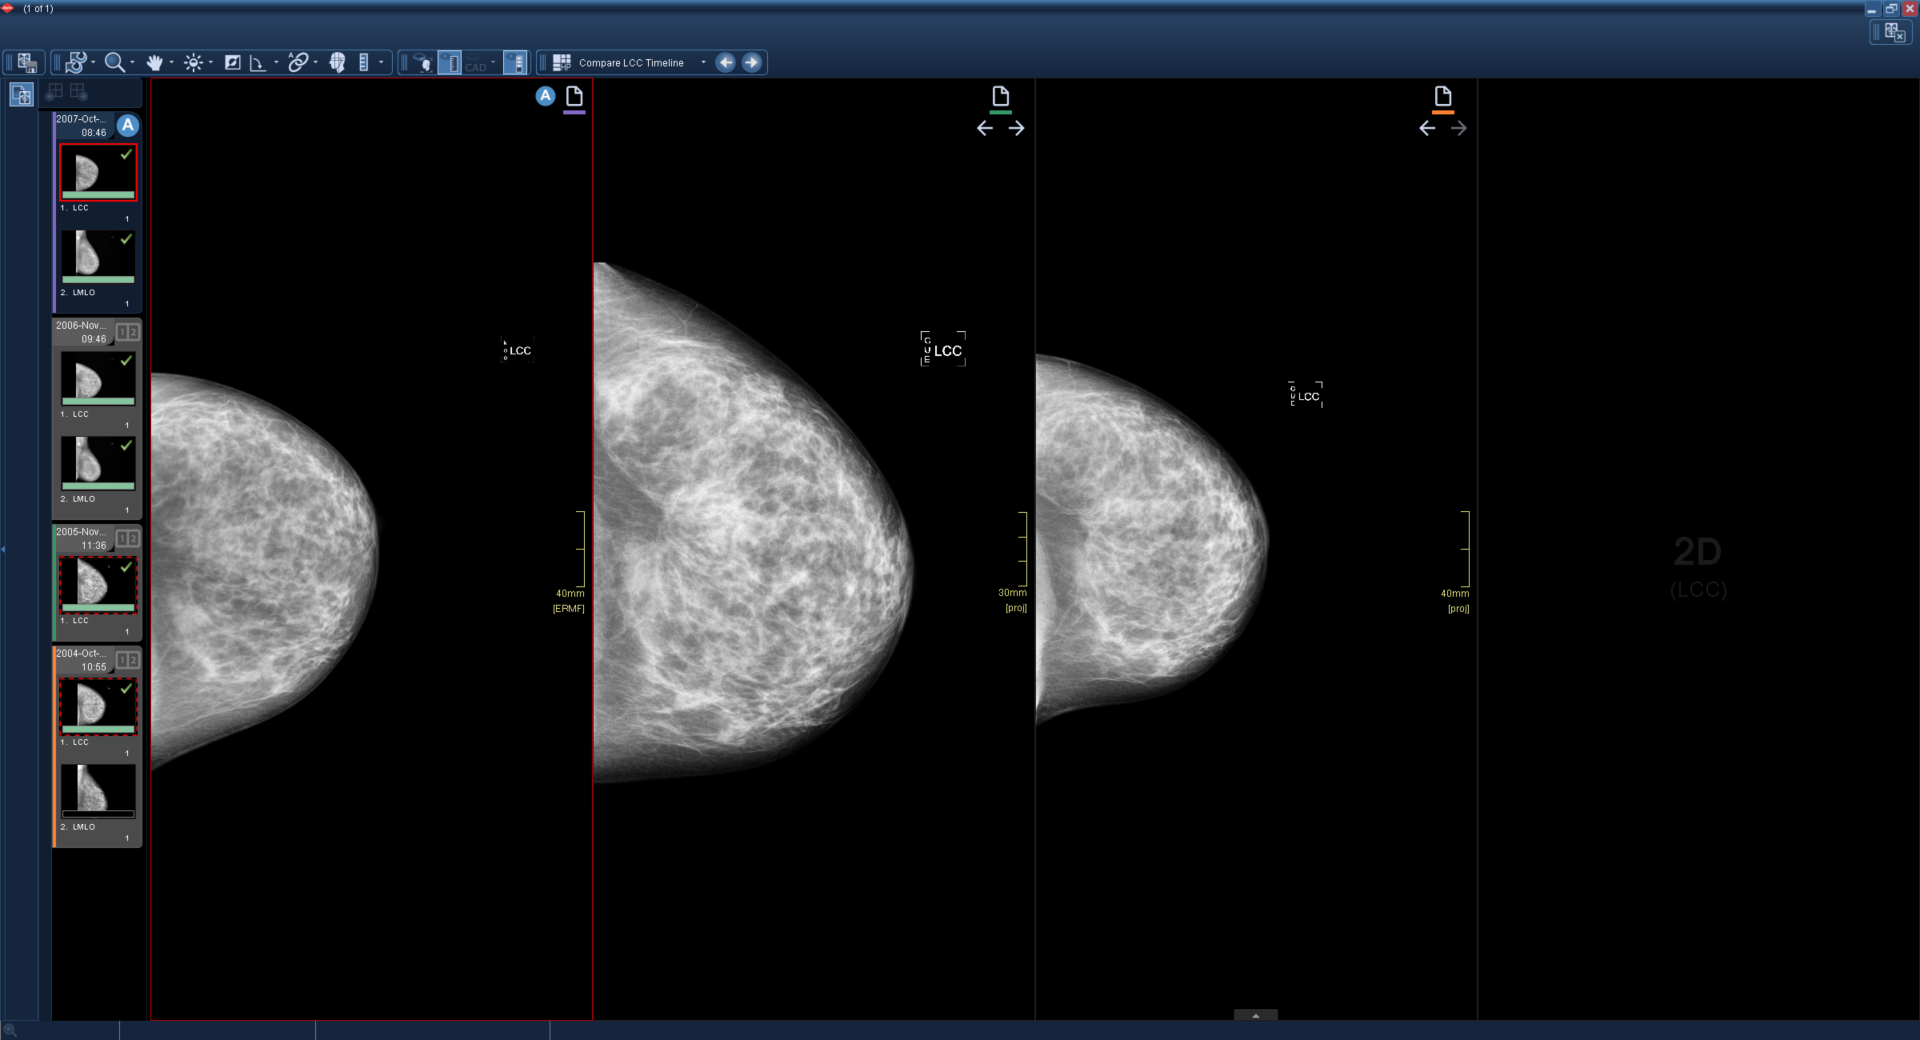

1

Μια ενεργή εξέταση με τρεις συγκριτικές εξετάσεις φορτώνεται και εμφανίζεται χρησιμοποιώντας το πρωτόκολλο ανάρτησης Compare LCC Timeline.

Χρησιμοποιώντας τη συντόμευση επόμενης συγκριτικής εξέτασης, όλα τα παράθυρα μετακινούνται στην επόμενη συγκριτική εξέταση. Όταν δεν υπάρχουν διαθέσιμες περαιτέρω συγκριτικές εξετάσεις, το παράθυρο είναι μαύρο.

Χρησιμοποιώντας ξανά τη συντόμευση επόμενης συγκριτικής εξέτασης, η τελευταία συγκριτική εξέταση μετακινείται δίπλα στο ενεργό παράθυρο. Όλα τα άλλα παράθυρα σύγκρισης παραμένουν μαύρα.

Η έγχρωμη γραμμή κάτω από το εικονίδιο εξέτασης παραμένει συγχρονισμένη με την πλαϊνή γραμμή κλινικών στοιχείων.